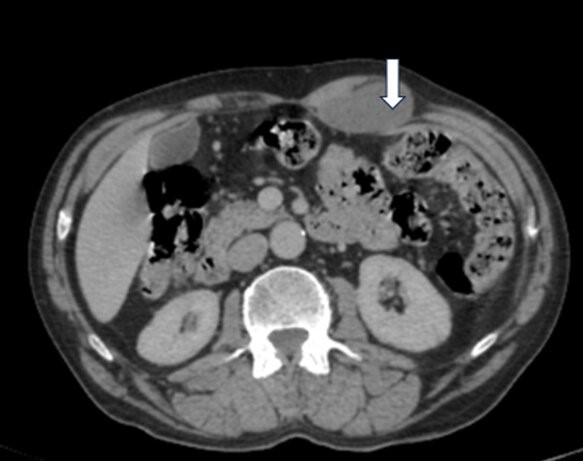

CT扫描示多个非典型位置的转移灶。这些转移灶在影像学上呈现出相似的特征,表现为低密度改变。转移灶的分布广泛,涉及心脏内部(右心室和左心室)、纵隔(后纵隔)、腹腔、左侧前腹壁以及右侧阴囊。

左侧前腹壁低密度病变,腹直肌受压移位(白色箭头)。